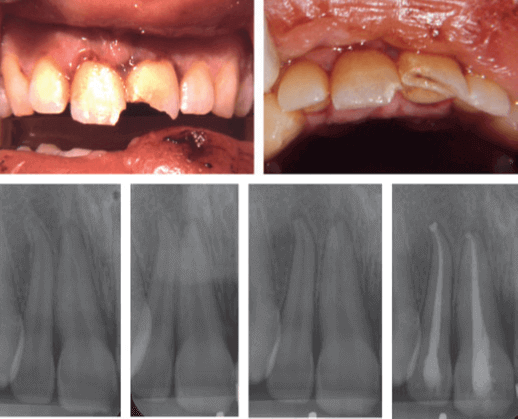

La concusión y la subluxación se describieron por primera vez en 1972 como tipos distintos de lesión del ligamento periodontal y de la pulpa. Una concusión se define como una lesión de las estructuras de soporte del diente sin aflojamiento ni desplazamiento anormales, pero con una reacción marcada a la percusión. Una lesión por subluxación se define como una lesión en las estructuras de soporte dental con aflojamiento anormal, pero sin desplazamiento dental.

Se supone que la etiología de una lesión por conmoción es un impacto menor en el diente, en el que la energía liberada solo ha provocado edema o sangrado y, en ocasiones, pequeñas laceraciones en el ligamento periodontal. La etiología de la subluxación es probablemente el resultado de un impacto menor en el ligamento periodontal, en el que la energía liberada provoca sangrado, edema y desgarro de las fibras del ligamento periodontal, lo que conduce a un aflojamiento anormal. Un estudio experimental en ratas ha demostrado estos cambios menores en el ligamento periodontal, así como sangrado en la capa odontoblástica cerca del foramen apical en dientes con concusiones y subluxaciones. Estudios previos sobre concusiones y subluxaciones se han centrado principalmente en la curación de la pulpa y las complicaciones pulpares.

La cicatrización periodontal tras una concusión y una subluxación solo se ha mencionado brevemente en relación con estudios previos sobre el pronóstico de los dientes permanentes luxados, que se centraban en el desarrollo de necrosis pulpar. La relación entre la reabsorción relacionada con la reparación y los dientes con lesiones múltiples podría estar relacionada con un diagnóstico insuficiente de la gravedad de la lesión por luxación en casos con múltiples dientes traumatizados. La diferencia entre una concusión y una lesión por subluxación se basa en una decisión subjetiva. Si varios dientes están involucrados en la lesión, la atención del examinador puede centrarse en los dientes con un diagnóstico más grave, por ejemplo, extrusión, luxación lateral, fractura alveolar o avulsión, y una subluxación puede, en este caso, clasificarse como una conmoción. En los dientes con una lesión por subluxación, la reabsorción relacionada con la reparación solo se produjo en los dientes con ápices cerrados y, en dos de los tres casos, también se observó necrosis pulpar. En estos casos, es posible que la reabsorción no esté causada por el traumatismo, sino que esté relacionada con la curación de una periodontitis apical derivada de la infección en el conducto radicular.

El bajo riesgo de reabsorción relacionada con la reparación indica que el daño causado por el traumatismo debió de ser muy limitado. De hecho, la frecuencia de reabsorción relacionada con la reparación no fue mayor en los dientes con lesiones por subluxación que en los dientes con lesiones por conmoción. En estudios de reimplantación en monos, la reabsorción relacionada con la reparación se ha localizado en áreas con lesiones moderadas del ligamento periodontal. También es interesante que los estudios histológicos de dientes humanos «normales» mostraron que la reabsorción relacionada con la reparación se encontró en casi todos los dientes. Estas áreas de reabsorción eran generalmente superficiales, lo que implica que no pueden diagnosticarse radiográficamente. En conclusión, el riesgo de complicaciones en la cicatrización periodontal tras lesiones por concusión y subluxación en la dentición permanente es muy bajo.